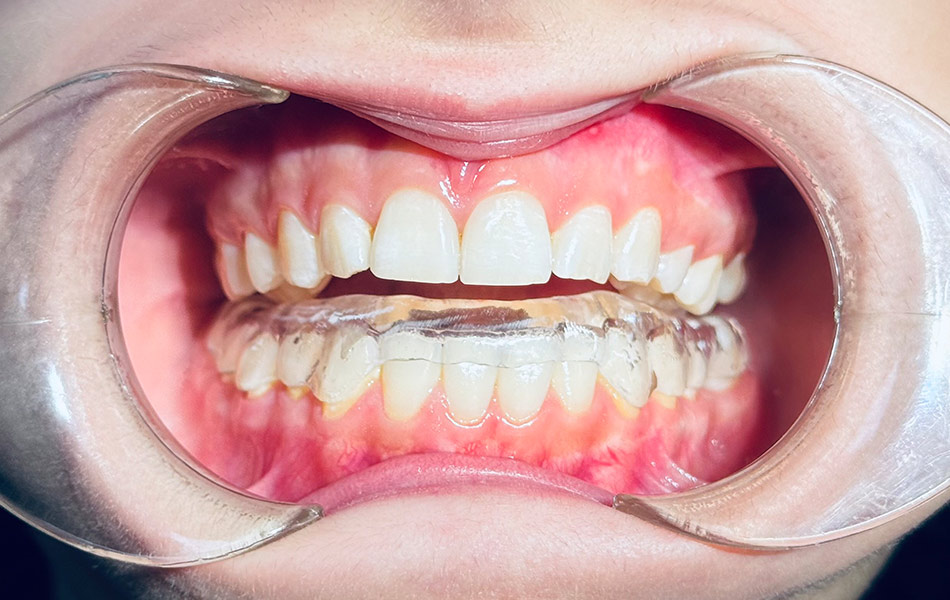

- Ограничение подвижности челюсти — специальные шины или сплинты для расслабления мышц;